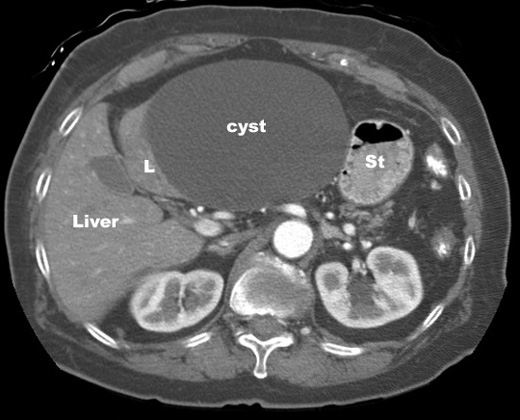

Liver Cyst

Large cyst left lobe of liver.

• Oval, Well Defined

• Imperceptible Or Thin Wall

• Water Density